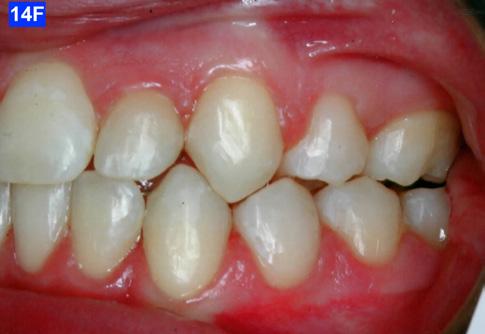

Please view the post-treatment images at the time of insertion of the retainers (Figure 14 - A, B, C. D, E, F, G, H, I, J, K, L, M, N).9

Figure 14F: Post-treatment, left lateral view